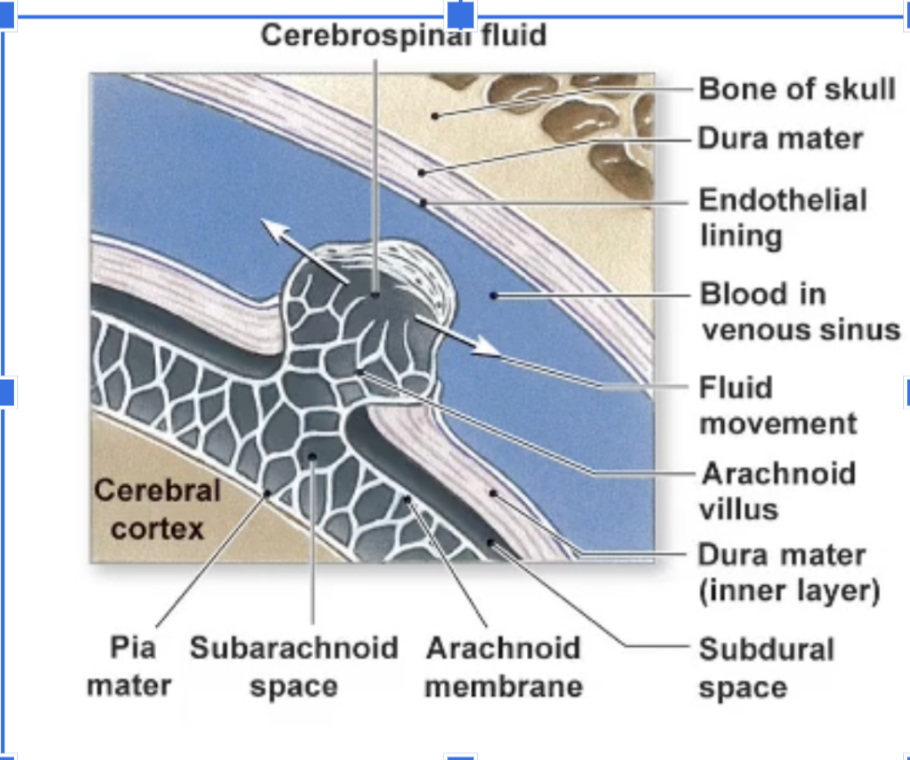

What are the three layers of the Cranial Meninges (thickest to thinnest)?

Dura Mater,Arachnoid Mater, Pia Mater

Which meningeal layer is thick, fibrous, provides physical protection, and is where brain bleeds occur when damaged?

The Dura Mater.

Which meningeal layer is thin, fibrous, looks like a web, and contains the cerebrospinal fluid (CSF)?

The Arachnoid mater

Where is the CSF located relative to the Arachnoid mater?

In the Subarachnoid space

Which meningeal layer is very thin, the deepest layer, and follows all the grooves of the brain?

The Pia mater.

How is excess CSF drained?

flows into the arachnoid villi where it is drained into dural venousus sinus with the blood